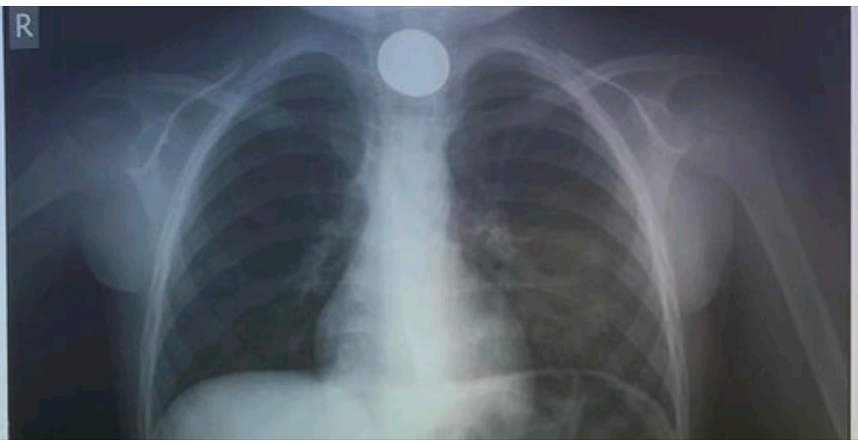

Περιπέτεια για οικογένεια, παραμονή Πρωτοχρονιάς, καθώς ένα 4χρονο παιδάκι κατάπιε κέρμα, με συνέπεια να μην μπορεί να αναπνεύσει.

Άμεσα μεταφέρθηκε στο νοσοκομείο, όπου οι γιατροί προχώρησαν και αφαίρεσή του.